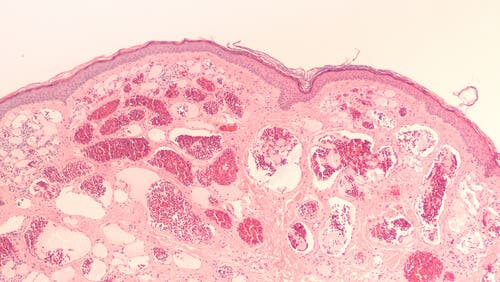

Estos tumores se desarrollan a partir de las vainas nerviosas —vainas de mielina—, un tipo de tejido que recubre los axones neuronales, los protege y facilita la transmisión del impulso nervioso. Si los analizásemos al microscopio, podríamos observar que están constituidos por una mezcla de células de Schwann, fibroblastos, células neurales y mastocitos.